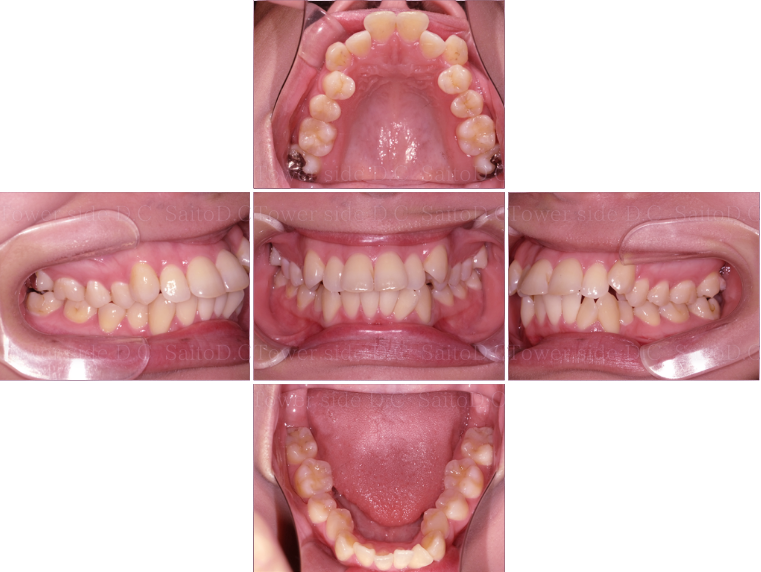

症例5CASE 5

|20代(女性)|

マウスピース矯正

症例(施術前)

症例(施術後)

主訴 八重歯が出ている

状況

• 前歯部叢生

• 上顎犬歯は低位唇側転位(八重歯)

• 口唇閉鎖不全有

治療費 1,030,700円(税込)(自由診療)

治療期間 2年8ヶ月

治療内容 14.24.34.44EXTを抜歯。矯正開始後1年経たずして遠方へお引越しとなったが、患者様のご希望があり当院でマウスピース矯正を継続。叢生、八重歯、臼歯部噛み合わせは改善され、その後保定装置(リテーナー)を使用し安定している。

リスク

• 歯根呼吸や、歯根の成長が阻害される可能性。

• 歯髄が壊死する可能性 歯の痛み、顎の痛み、虫歯、歯周病、矯正器具により口腔粘膜の傷、喋りにくさが生じる可能性。

• 矯正治療後は、リテーナーを使用しないと歯の位置に後戻りが生じる可能性。